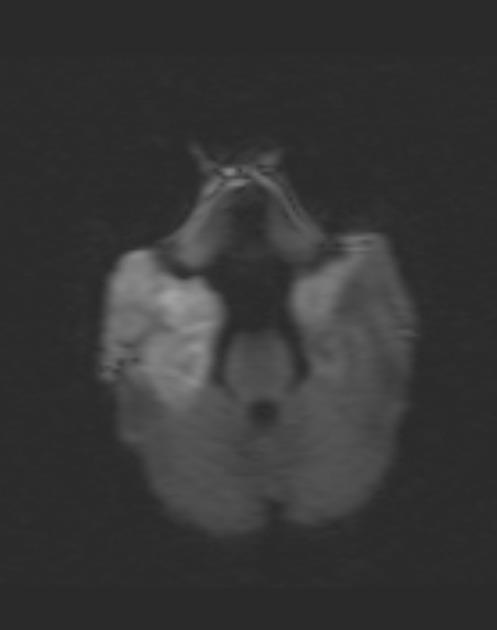

• Ранние изменения: отек, изменения на ДВИ

• Вариабельная степень вовлечения головного мозга, ранние изменения на ДВИ

• Вариабельные изменения со стороны БВ, СВ (кора, БГ), височных долей, ствола мозга, мозжечка ± зон водораздела:

- рестрикция диффузии (повышение сигнала в ДВИ последовательностях, подтвержденное при ИКД), как правило, диффузная и двусторонняя;

В группе пациентов, у которых развился неонатальный герпетический энцефалит в течение 28 дней после рождения, основными признаками при использовании DWI-последовательности были кортикальные поражения. Двустороннее поражение глубоких слоев коры и белого вещества мозга, визуализируемые на 7-й день, были предикторами плохого прогноза и высокой вероятности развития двигательных и когнитивных расстройств.